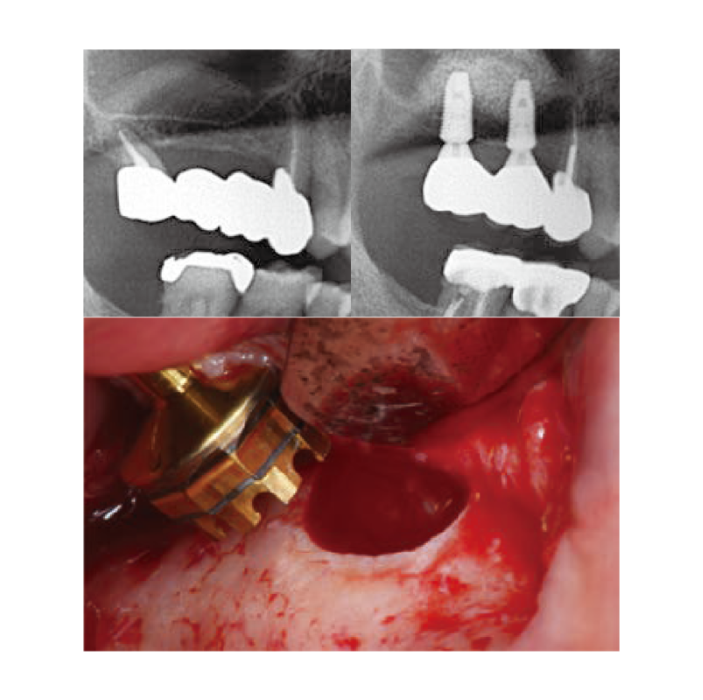

Wall-off Technique

Wall-off Technique